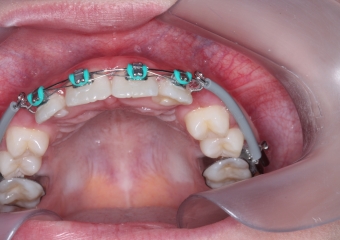

Cirurgia com fio de aço instalado para tracionamento dos caninos permanentes

Dentes em tracionamento